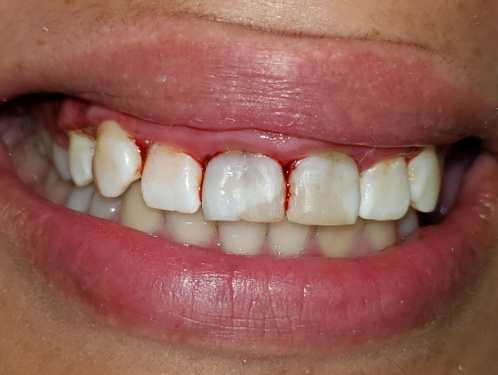

Paciente femenina de 28 años acude a la Facultad de odontología por motivo estético y molestia en el sector anterior y es derivada la asignatura Endodoncia B. Refiere alteración en la coloración de sus incisivos superiores y vergüenza al sonreír y molestia al morder con sus dientes delanteros. Al examen clínico, se observa restauración defectuosa y coronas manchadas (Fig 1-2). La paciente relata una caída hace más de 10 años, tras la cual le realizaron una reparación dental con tornillos metálicos.

Fig. 1 foto inicial Vestibular

Fig. 2 Foto inicial vest y palatina